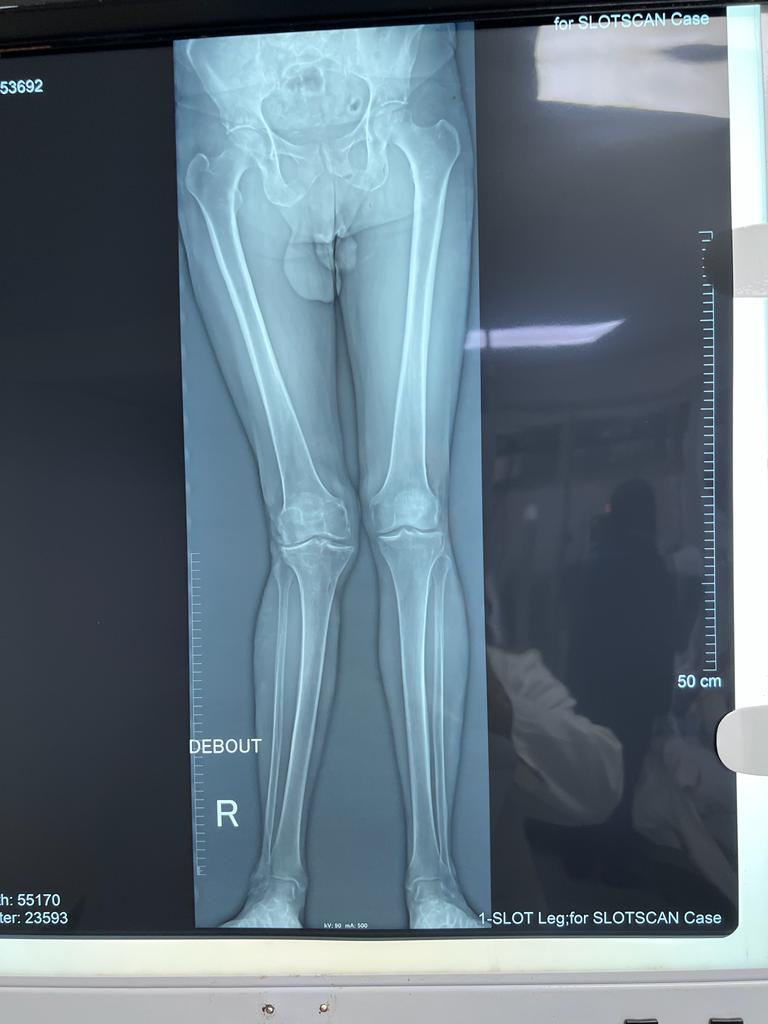

Total Knee Arthroplasty on a severe Genu Valgum

• Total Knee Arthroplasty on a severe Genu Valgum